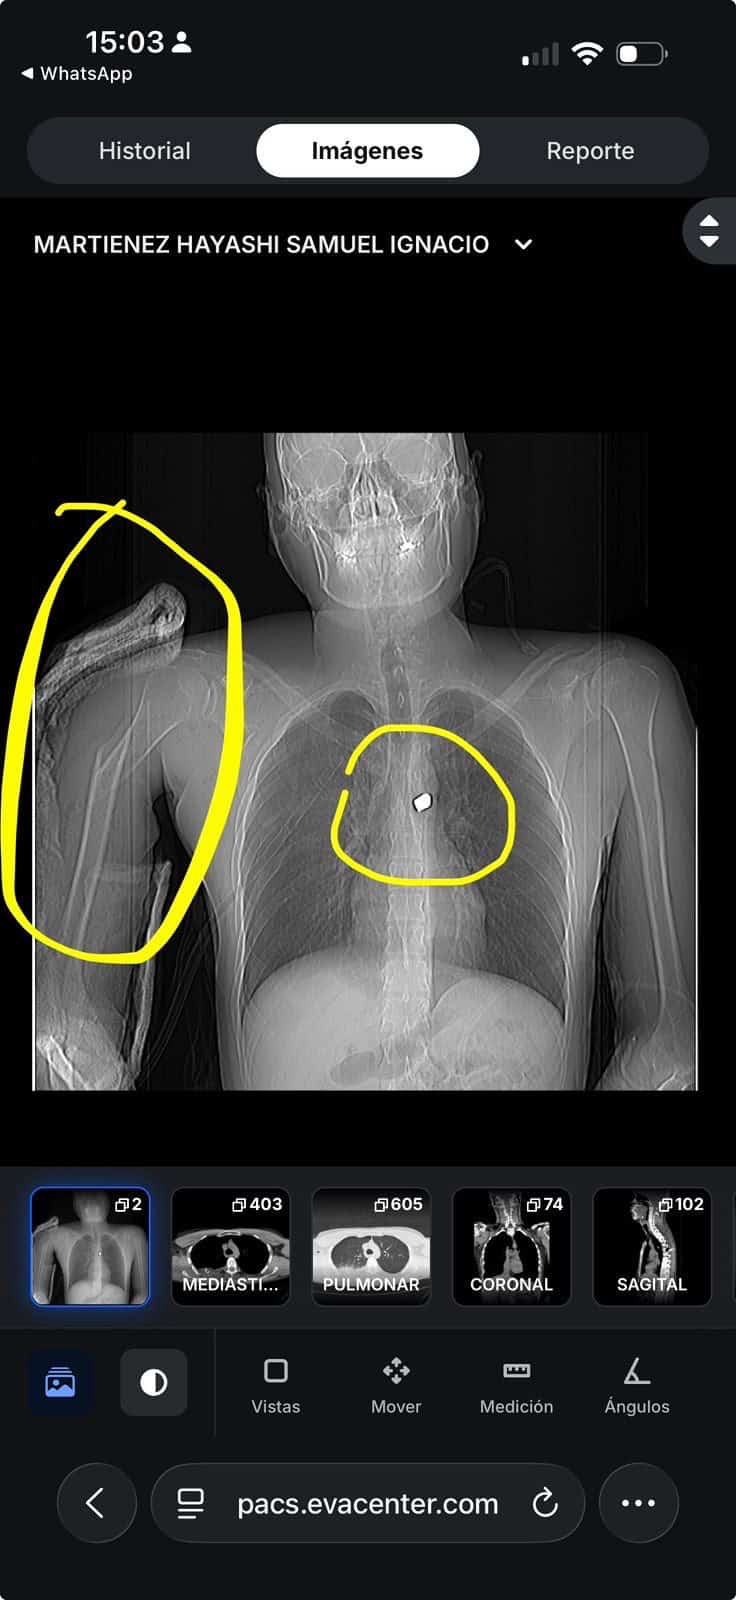

Samuel Martínez fue atacado el pasado 21 de abril en la colonia El Florido Tercera Sección, luego de retirar 50 mil pesos de una sucursal bancaria. De acuerdo con reportes locales, cuatro hombres lo interceptaron para despojarlo del dinero y uno de ellos le disparó a corta distancia, provocándole heridas en un brazo, el pulmón y la médula ósea.